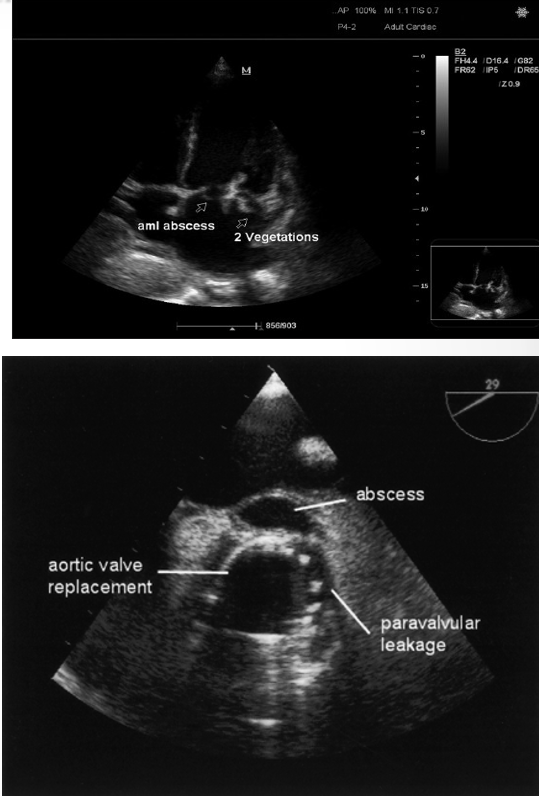

what do IE abscesses look like?

nonhomogenous enclosed area appearing echolucent or echodense

what is this?

abscess

what is shown here?

ao valve vegetation with abscess